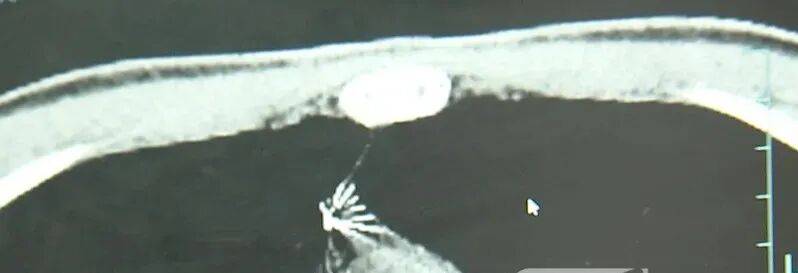

近日,安徽17岁小伙小陆参加征兵体检,胸片结果显示:胸腔内有一处金属高密度影,形态细长,像一根针偿债基金系数。

进一步的CT检查确认,异物是一枚金属针,斜插在肺组织内,位置十分凶险偿债基金系数。

杭州市第一人民医院心胸外科副主任冯兴说:“我们看到这个针的尖锐部,正好指向他体内的一个大血管,边上是上腔静脉和胸主动脉,因此这个针稍有不慎,就有可能造成周边血管的损伤,甚至危及生命偿债基金系数。”